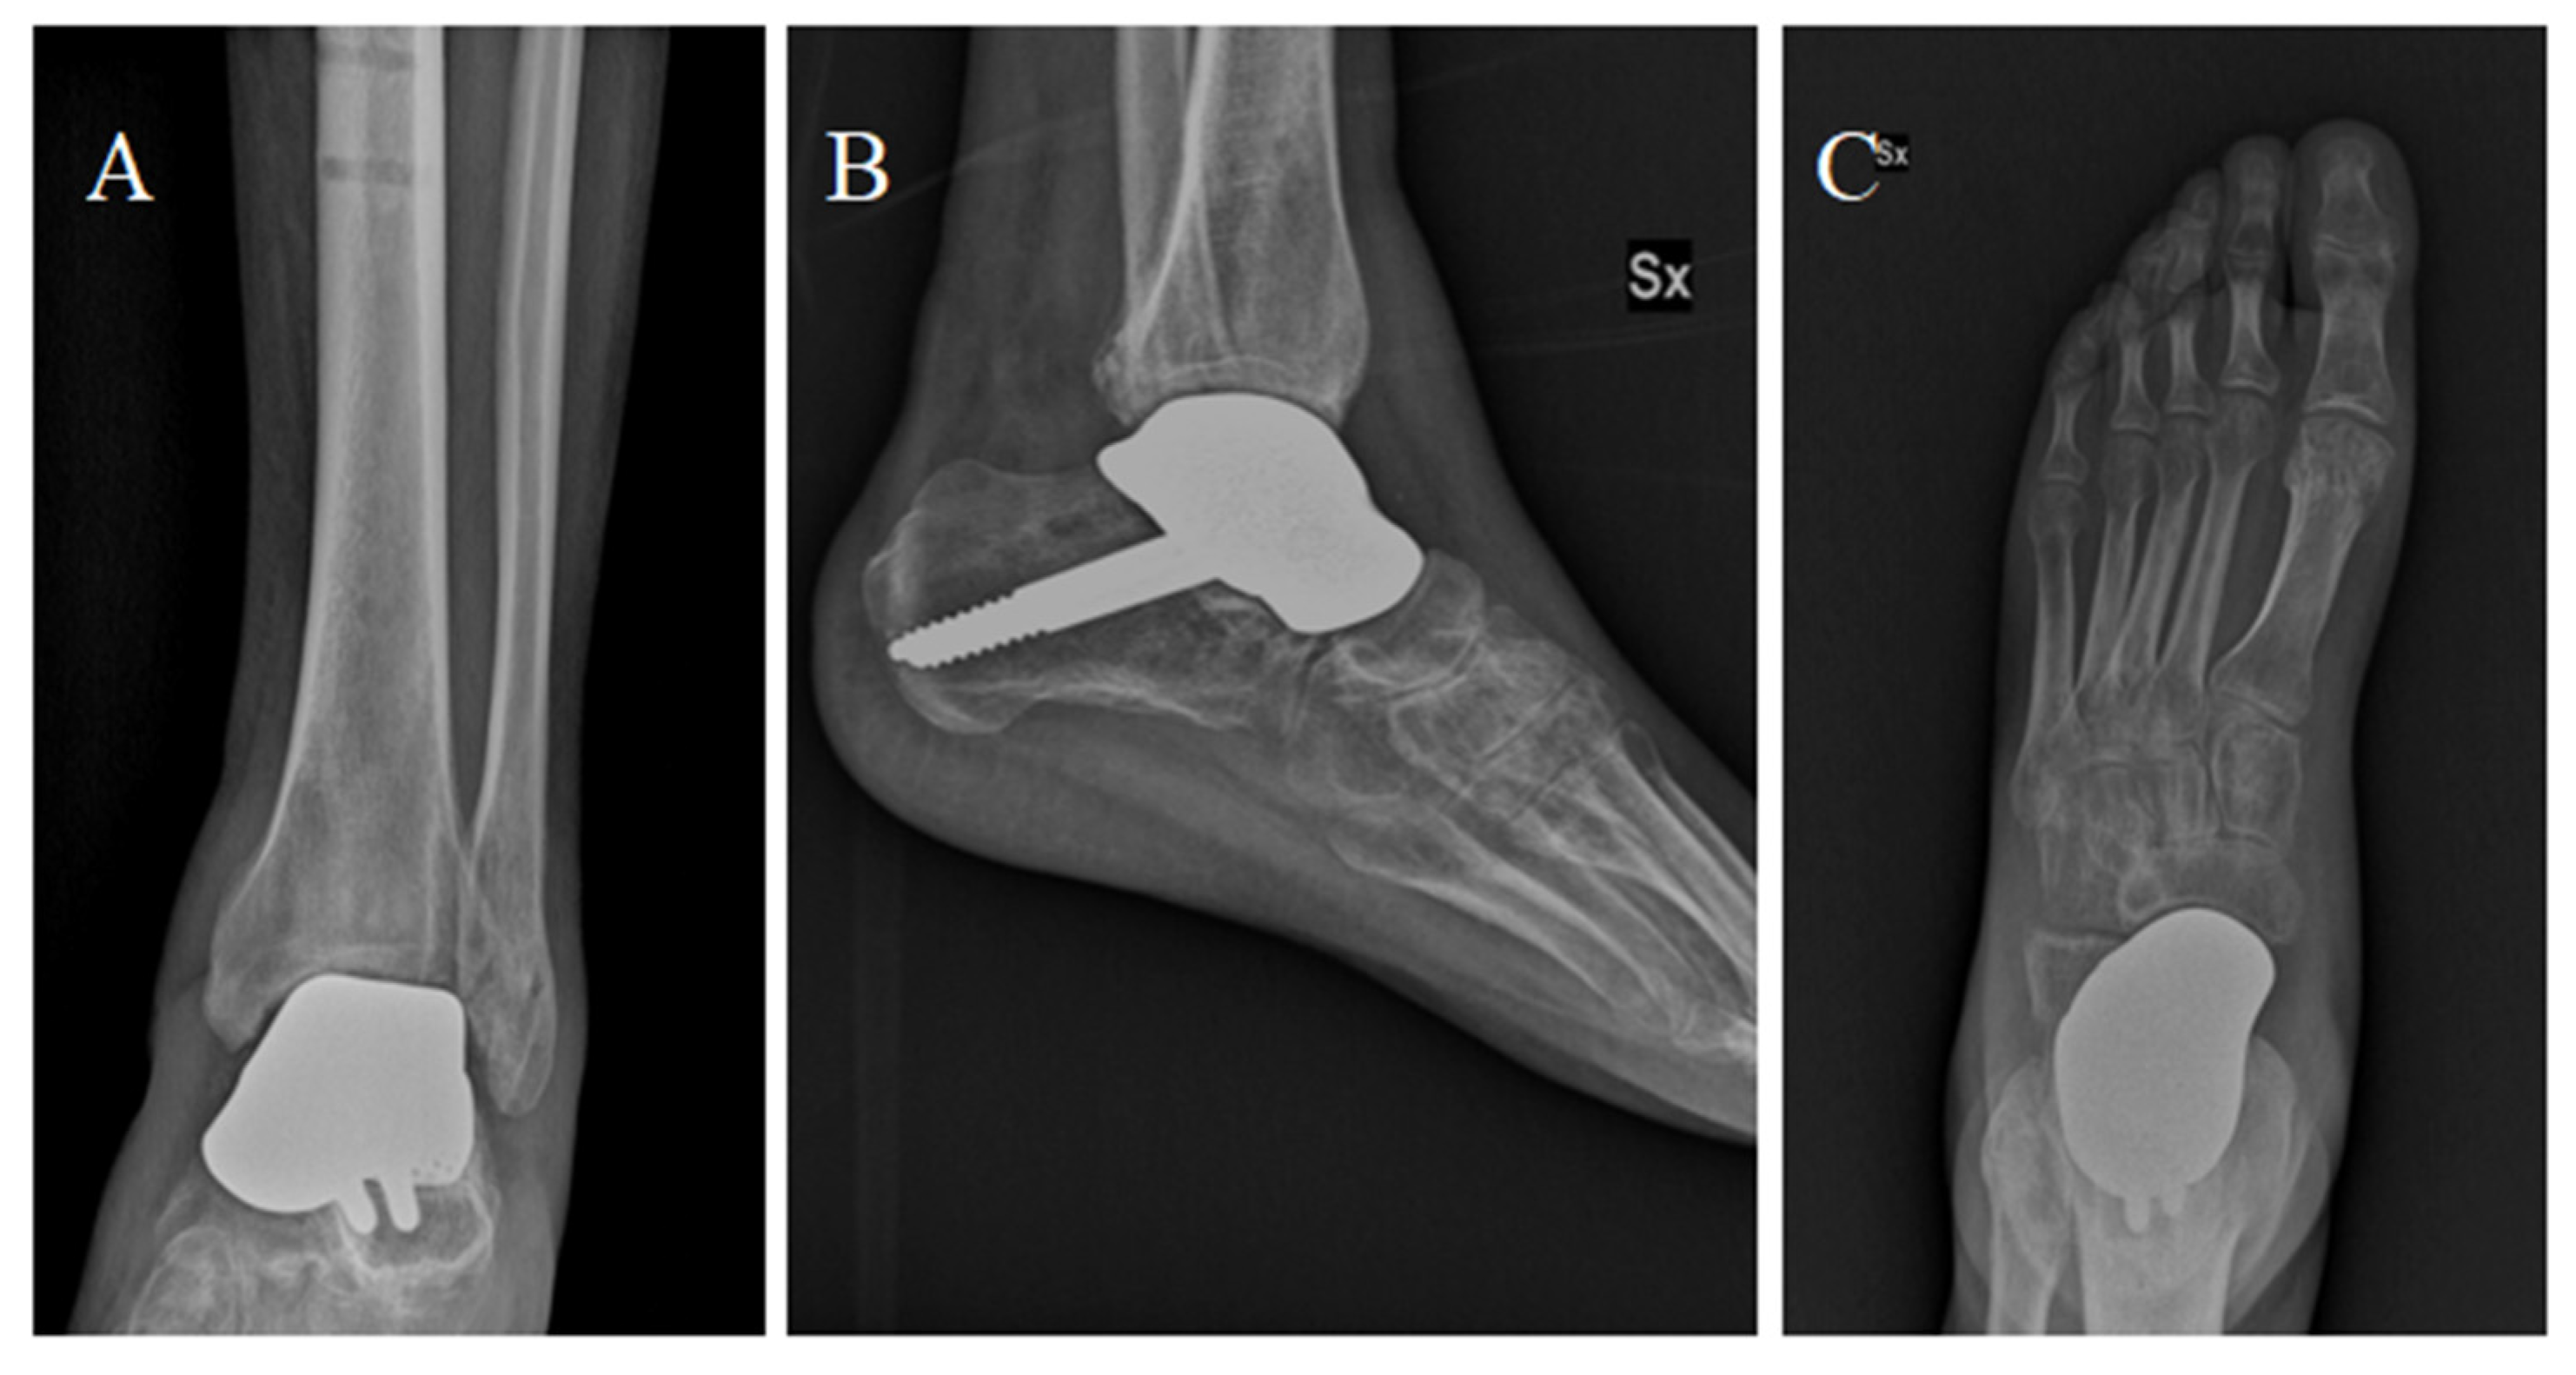

Figure 5.

Anterior-posterior (A), dorsoplantar (B) and latero-lateral (C) projections showing the implant at the 6-month follow-up after surgery.

Percutaneous Achilles tendon lengthening was performed to improve ankle dorsiflexion. After surgery, a plaster cast was applied for 3 weeks. After 3 weeks, partial weight bearing was allowed, with full weight bearing within 9 weeks of surgery. We decided to examine the patient at 1, 2, 4, 6, and 12 months after surgery, and then once a year (Figure 5). The patient was satisfied with the outcome of the surgery and showed good functional results: At 6 months, he presented an AOFAS (American Orthopedic Foot and Ankle Society Score) of 86 and an NRS (Numeric Rating Scale) of 2. The sagittal range of motion (ROM) was >30°. The patient satisfaction as well as the clinical scores were retained at the 12-month follow-up.